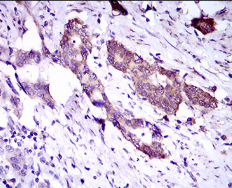

| AC2092 | DNAL4 Mouse Monoclonal antibody[3C24] | 100ug | $367 | 10days |

| AC2092 | DNAL4 Mouse Monoclonal antibody[3C24] | 200ug | $660.6 | 10days |